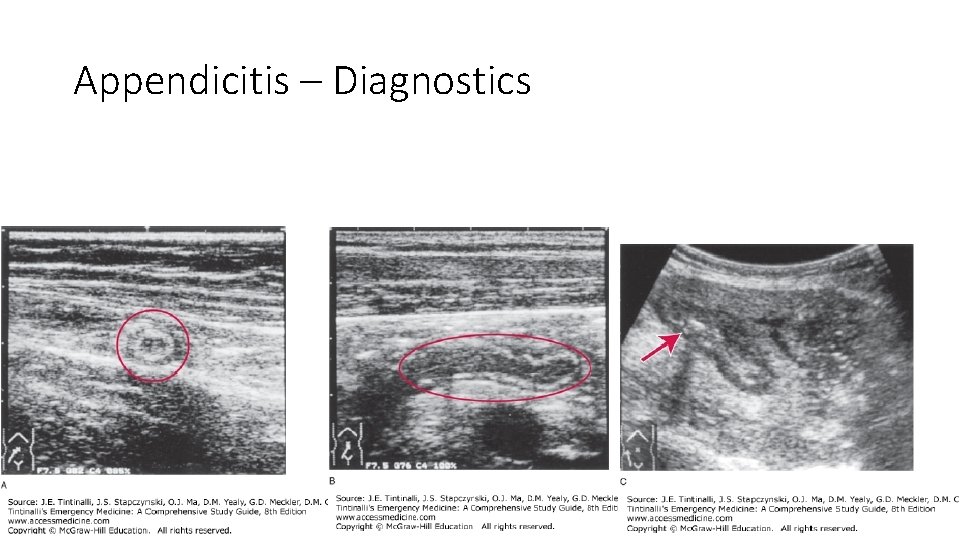

Appendicitis – Diagnostics Imaging • Not always necessary in straightforward cases, children • US • Initial imaging of choice for pregnant and children; also nonobese • Safe, fast, well tolerated, costeffective • Normal Appendix Features: absence of peristalsis, lack of change in configuration, small • Appy Findings: thickened, noncompressible appendix >6 mm in diameter, sometimes identifies appendicolith, surrounding edema • Better at ruling in than out • Limits: operator skills, retrocecal appy, perf, excessive guarding, bowel gas, gravid uterus, obese • Sn 86%, PPV 95%

Appendicitis – Diagnostics